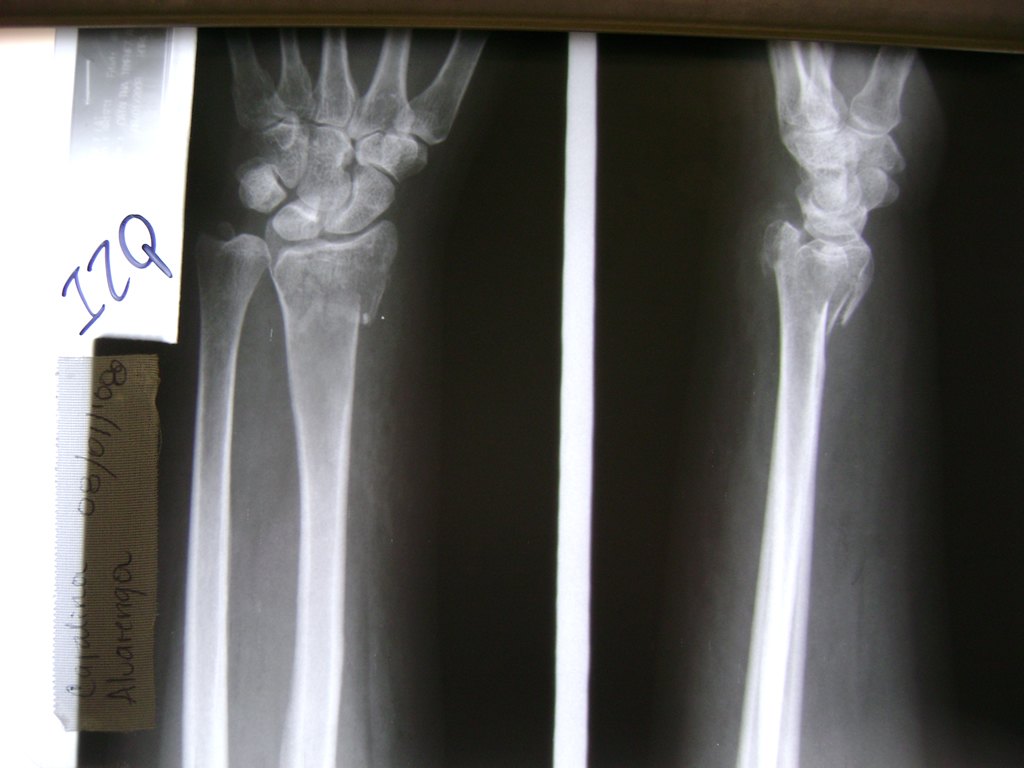

Cirugías de Codos - Cirugías de Muñecas y Manos

Los procedimientos más comunes en cirugía de la mano son aquellos destinados a reparar traumatismos, incluyendo lesiones de tendones, nervios, vasos sanguíneos, y articulaciones; huesos fracturados; y quemaduras, cortes, y otros daños de la piel.